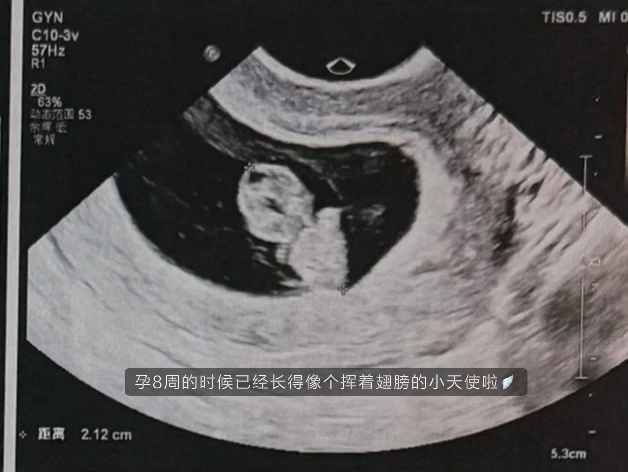

12月底就发现已经怀孕4周了